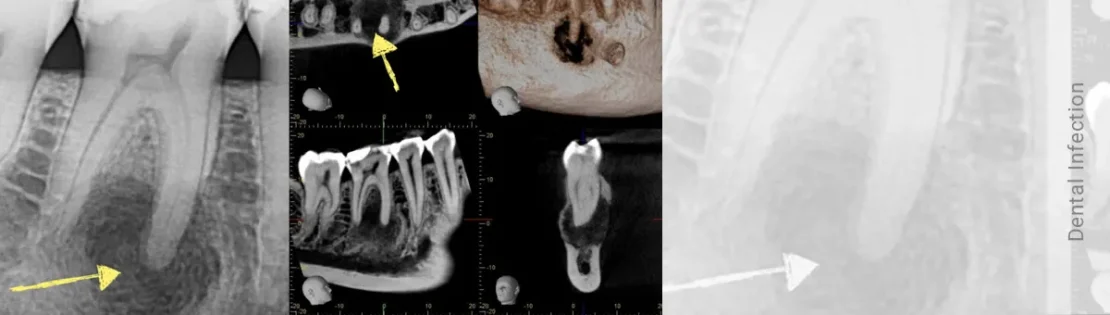

- تصویربرداری با اشعه ایکس (رادیوگرافی): تشخیص میزان گسترش عفونت و درگیری ریشه یا استخوان اطراف